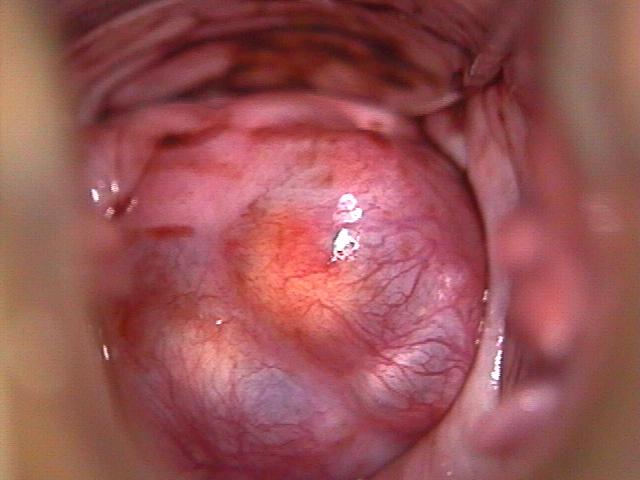

After the cervix is studied with the colposcope, the cervix is washed with a chemical called 3 – 5% acetic acid. The acetic acid dissolves mucus and stains the abnormal areas white. (acetowhite lesions). Staining with a dilute iodine solution (known as Lugol's solution or Schiller's solution) is also performed to further examine for abnormalities. Normal cells will generally take up the iodine stain (and turn brown) in a uniform manner, whereas severe precancerous and cancerous areas will not.

2. Use of color filters

Color filters help the physician examine tiny blood vessels (capillaries) in the area of the squamocolumnar junction. Blue or green filtered light can cause abnormal capillaries to become more obvious, usually inside an acetowhite area. Normal capillaries are slender and spaced out evenly. In contrast, abnormal capillaries can appear as red spots (thickened capillaries seen on end) or can produce a pattern resembling hexagonal floor tiles.